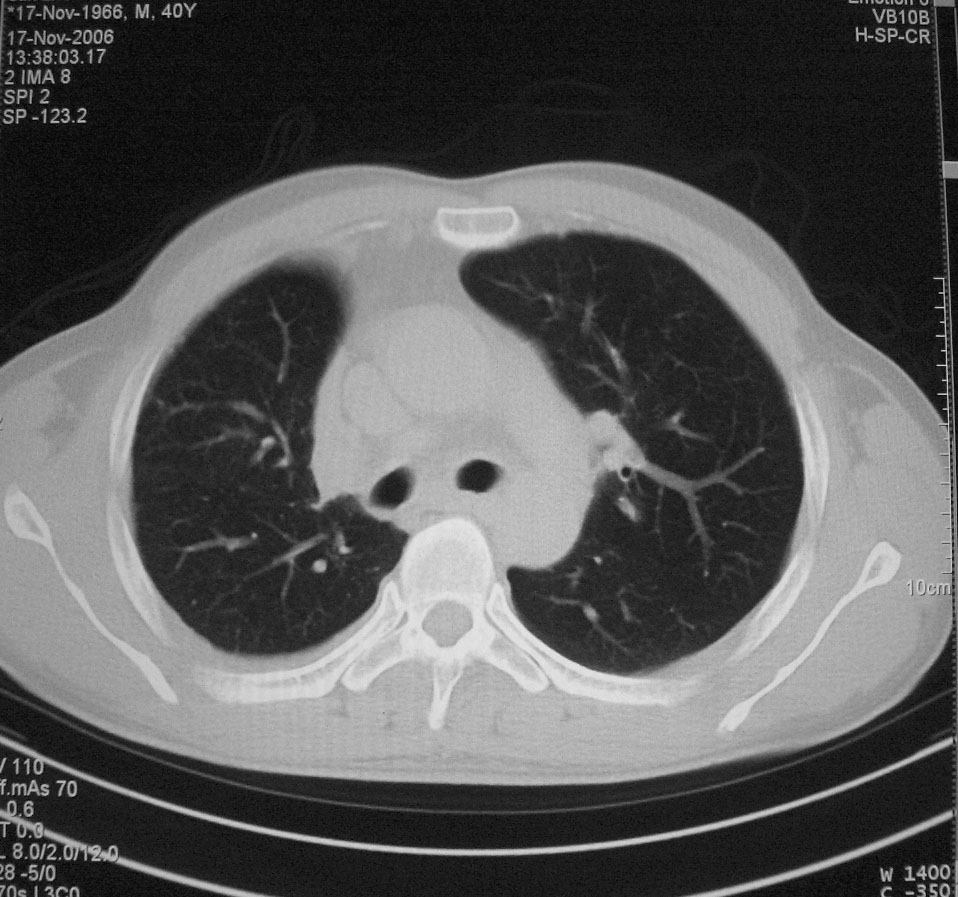

标题: CT5485:[原创]肺部占位请讨论

右上肺ca并肺不张,纵隔淋巴结转移

右肺上叶中央型肺癌并上叶肺不张、纵隔淋巴结肿大

右上叶支气管后壁明显增厚,支持右肺上叶中央型肺癌伴右上叶肺不张、纵隔淋巴结肿大。

右上叶支气管后壁明显增厚,支持右肺上叶中央型肺癌伴右上叶肺不张、纵隔淋巴结肿大。建议支气管镜检查。

右上肺中央性肺癌伴右侧胸腔少量积液!右上肺胸膜下还有一小病灶,不完全排除结核,但个人支持恶性肿瘤!建议早穿刺活检。

右上叶支气管开口变窄,纵隔见肿大的淋巴结。支持右上叶中心型肺癌并右上叶不张纵隔淋巴结肿大。

右肺上叶中央型肺癌并上叶肺不张、纵隔淋巴结肿大.右侧少量胸腔积液。

右肺上叶支气管后壁增厚,呈鼠尾状狭窄,纵隔内未见明显增大的淋巴结影,考虑为中央型肺癌伴右上肺不张